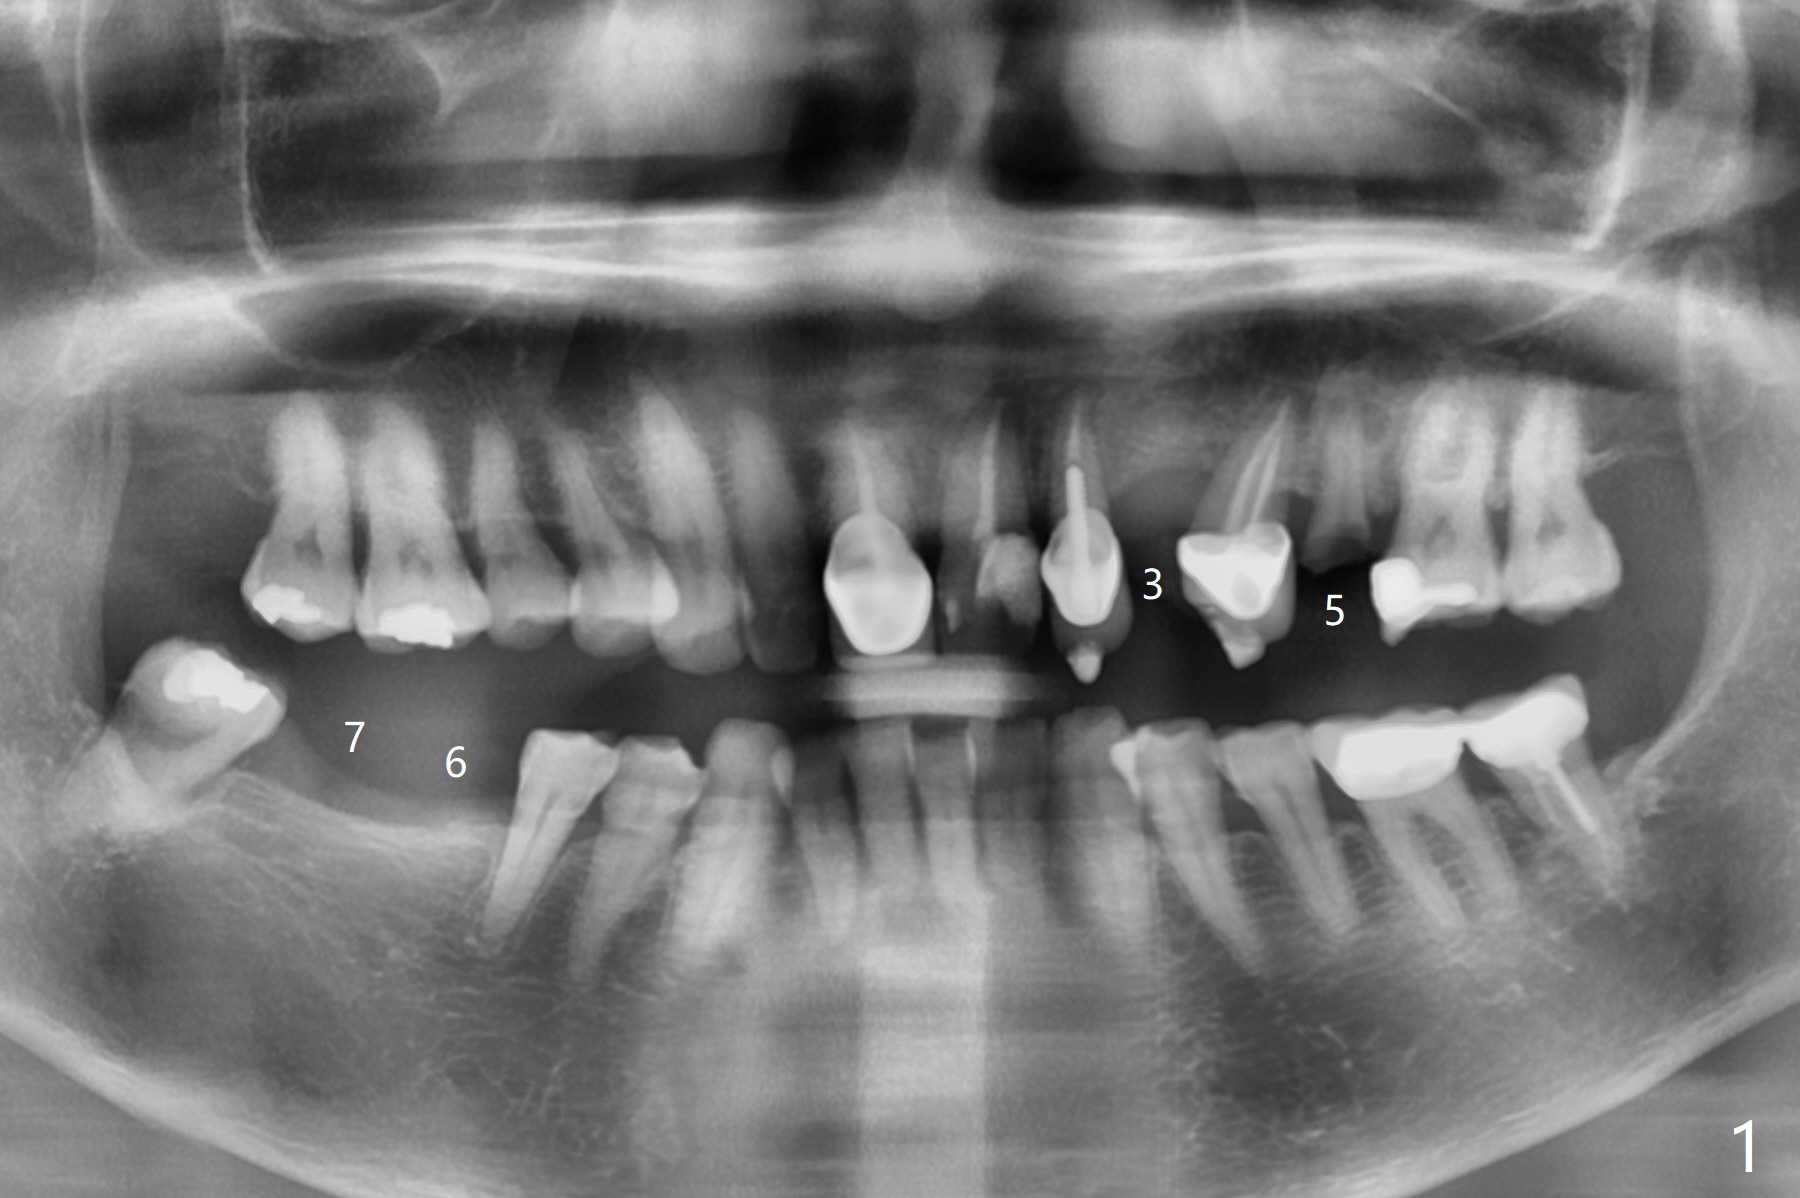

63岁女需要四个植牙(图一:左上3,5,右下6,7),由于3牙槽嵴狭窄,选择导板种植。5根尖阴影,颊侧骨板穿孔(图二:箭头)。即种时如何修复?骨粉,植体,哪个先放